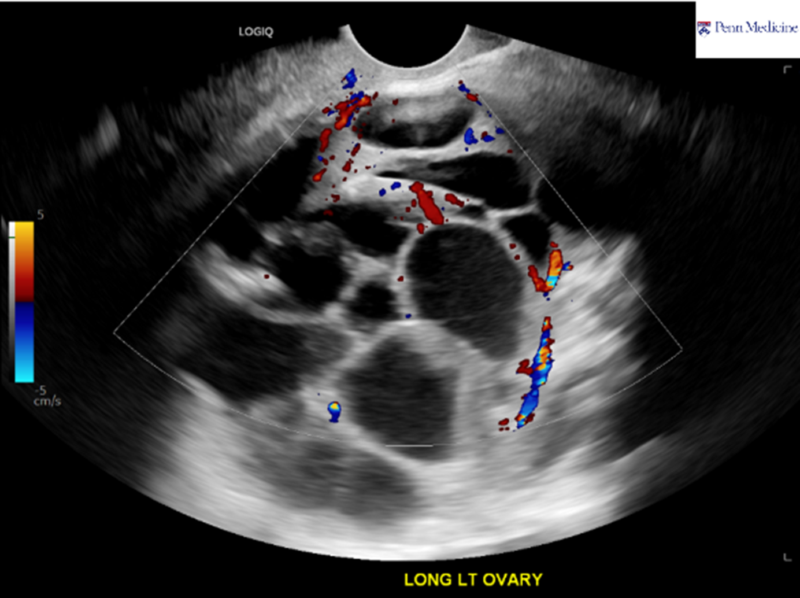

A 56-year-old man with history of coronary artery disease, myocardial infarct, hypertension, hyperlipidemia, and heart failure presented to the emergency department for painful swelling of his scrotum for a week with generalized myalgias, fatigue, and dysphonia, with the development of a large lymph node in the left supraclavicular region.